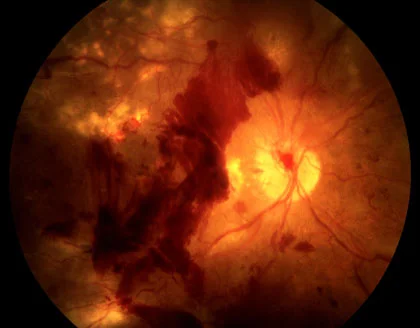

3. Proliferative Diabetic Retinopathy

This advanced stage is characterized by the growth of abnormal new blood vessels (neovascularization). These vessels are fragile and prone to bleeding, which can lead to vitreous hemorrhages, retinal detachment, and severe vision impairment. Immediate consultation with a retina specialist is crucial at this stage.

Can diabetic retinopathy cause blindness?

Yes, diabetic retinopathy can lead to blindness if left untreated. Advanced stages of the condition, such as proliferative retinopathy, involve the growth of fragile, abnormal blood vessels that may bleed into the eye or cause retinal detachment. Macular edema, where fluid builds up in the central retina, can also severely affect vision. Although vision loss cannot be reversed, timely interventions like laser therapy, injections, and surgery can significantly reduce the risk of blindness. Early detection through routine screenings and strict diabetes management is the most effective way to protect sight and prevent irreversible vision loss.

Can diabetic retinopathy lead to retinal detachment?

Yes, diabetic retinopathy can increase the risk of retinal detachment, particularly in proliferative stages. Abnormal blood vessels may grow on the retina and form scar tissue. Over time, this tissue can contract, pulling the retina away from its normal position, causing traction retinal detachment. Symptoms may include sudden flashes of light, floaters, or a curtain-like shadow across vision. Retinal detachment is a serious complication that requires urgent surgical intervention, such as vitrectomy, to prevent permanent vision loss. Regular eye exams can detect early signs and allow timely treatment to reduce the risk of detachment.